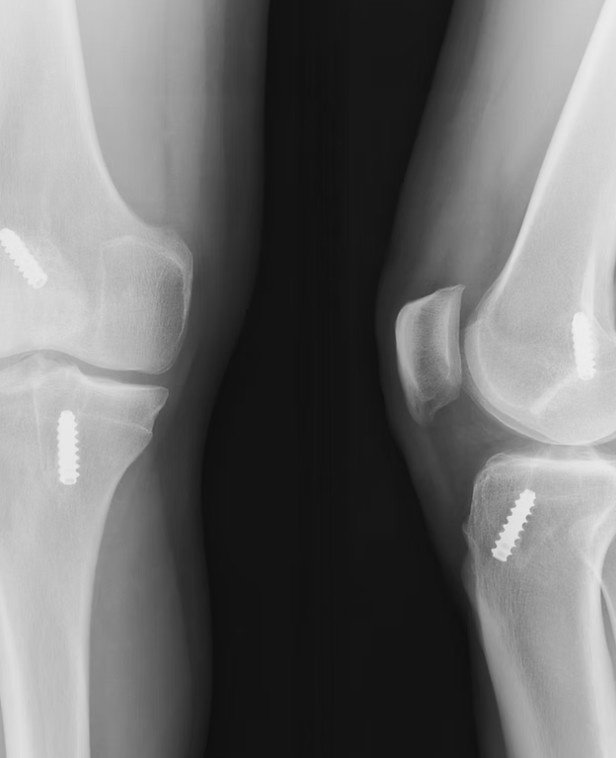

Successful ACL reconstruction begins long before the actual surgery. Dr. Guruditta Khurana conducts a detailed pre-operative assessment, which includes:

- Clinical examination

- Imaging studies such as MRI

- Evaluation of associated injuries (meniscus or cartilage damage)

This thorough evaluation helps in precise surgical planning and avoids complications. Patients searching for the Best ACL Reconstruction in Gurugram value this structured and transparent approach, as it builds trust and clarity from the very beginning.